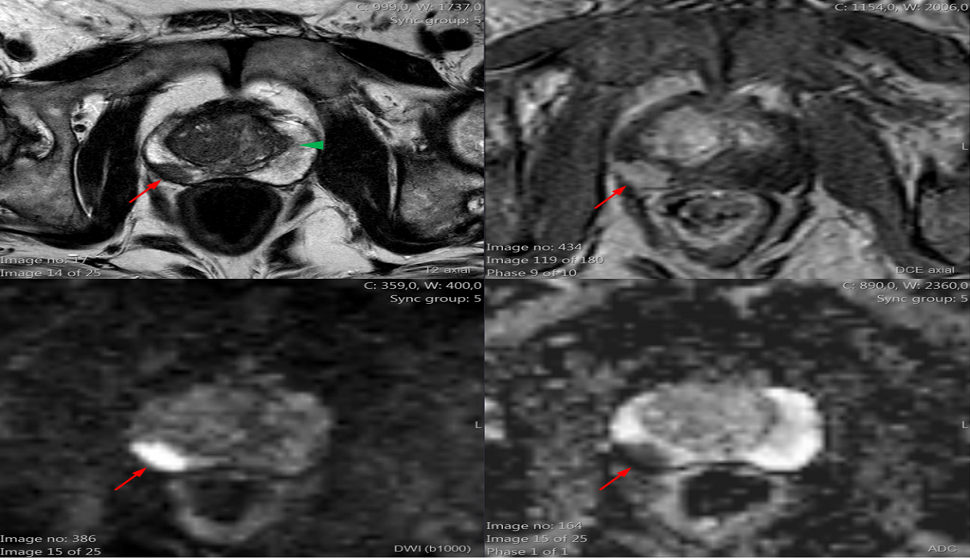

ESTUDO DA PROSTATA PELA RESSONÂNCIA MAGNÉTICA Prof. KERLA AFFONSO A ressonância magnética (RM) da próstata é uma técnica de imagem avançada que é frequentemente utilizada para avaliar a próstata, especialmente para a detecção e caracterização de doenças da próstata, como …